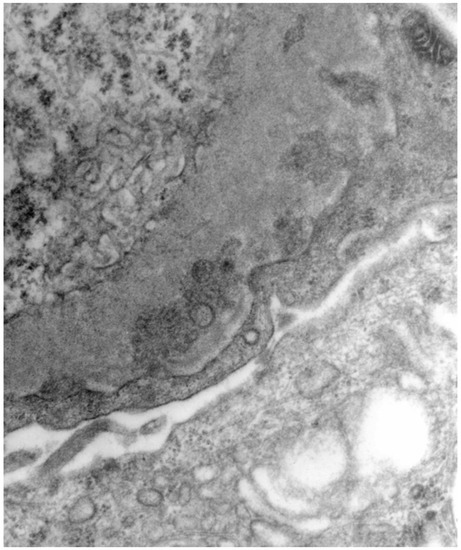

3.2. HBV-Related Membranoproliferative Glomerulonephritis (MPGN)

- Li, C.; Li, H.; Su, W.; Wen, Y.B.; Ye, W.; Ye, W.L.; Cai, J.F.; Qin, X.Z.; Li, X.M.; Li, X.W. Clinicopathological study of mixed cryoglobulinemic glomerulonephritis secondary to hepatitis B virus infection. BMC Nephrol. 2020, 21, 395. [Google Scholar] [CrossRef] [PubMed]